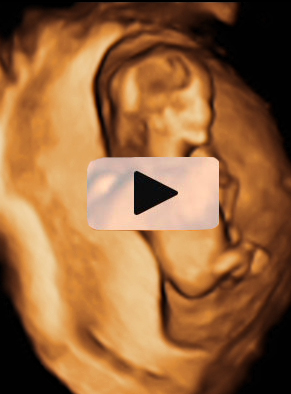

Ecografía 4D semana 12: Bebé con cordón umbilical al cuello

Ecografía en 3D de feto de 13 semanas con el cordón umbilical al cuello

La ecografía en tres dimensiones muestra un feto de 13 semanas de gestación con el cordón umbilical alrededor del cuello. En la imagen rotatoria se puede observar la situación del cordón, que sube por el tórax y que seguramente puede causar complicaciones en el embarazo.